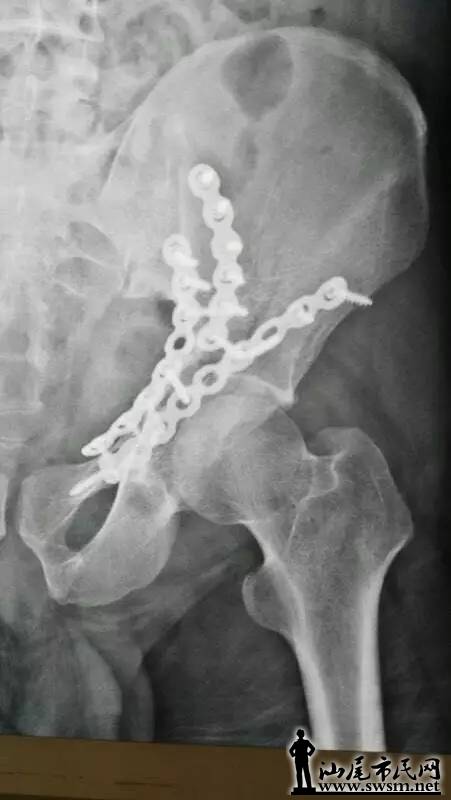

海丰县中医医院骨三科团队,利用3D打印技术,事先将患者的骨盆CT扫描数据输入电脑,再用先进的3D打印机,以1:1比例打印出熊先生的仿真骨盆模型。预先为其设计好最佳的手术治疗方案。                   640.webp.jpg                                                                          ( 上图:术前DR片)                                                                                                                   640.webp (1).jpg       640.webp (2).jpg                                                 (上图:术前CT片)

骨三科团队手术前在仿真骨盆进行虚拟手术,设计好钢板旋转的最佳位置、螺钉植入的最佳方向,并进行钢板、螺钉长度的数据测量,螺钉方向导航模块的设计及钢板预弯等一系列术前体外模拟手术,所有准备工作操练完毕,最后才正式为其施髋臼骨折复位钢板内固定手术。                                     640.webp (3).jpg                                                                                  (上图:虚拟手术,预弯钢板、测螺钉长度等数据)

由于钢板放置最佳位置、螺钉长度等已按照伤者的身体进行过精准的测量,减少了不必要的显露,手术切口仅8厘米;手术中也不需要反复预弯钢板和测定螺钉,使得手术时间大大减少。真正的内固定手术不到1小时,另外前后出血不足600毫升,大大节约血源、减少输血风险等,提高了手术的安全性,减少了伤者的痛苦。                                                                                        640.webp (4).jpg 640.webp (5).jpg 640.webp (6).jpg 640.webp (7).jpg                                                                          从术后复查钢板位置及螺钉植入方向、长度与术前3D打印模拟手术完全匹配,患者术后第二天便可以自行翻身、半坐等,良好的疗效受到了患者及其家属的称赞。